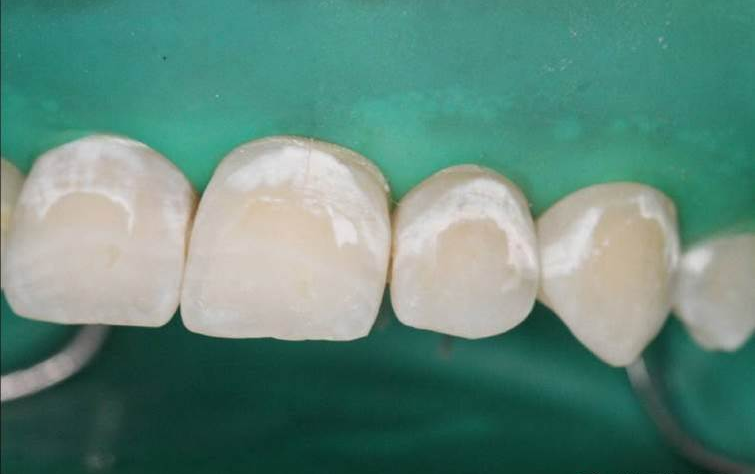

5、干燥后的牙面

dmg口腔材料怎么使用DMG-Icon专利之渗透树脂(内含操作视频)_https://www.jmylbn.com_新闻资讯_第10张